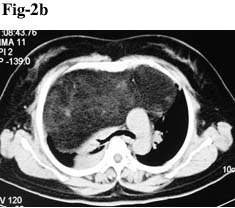

Her past history revealed that in the year 2002, the patient had a thoracotomy for anterior mediastinal mass. The patient was admitted with the same complain and a chest X-ray (Fig. 2a) and subsequent CT scan (Fig. 2b) revealed a large lesion mostly in right hemithorax and partly on the left side with evidence of compression on superior vana cava and pulmonary arteries with their posterior displacement. Significant lung compression was also present at that time. The patient underwent right sided thoracotomy on February 2002. The encapsulated mass was completely excised including the capsule. Histopathology revealed lipoma and no evidence of malignancy. Post operative recovery was uneventful with satisfactory lung expansion. The patient was alright for the last few years but again developed the same complaints of dyspnoea (2009) and was admitted in the hospital once again. As mentioned ealier, X-ray and CT scan revealed a lipomatous lesion which was subsequently cinfirmed by CT guided FNAC. The final radiological diagnosis was recurrence of mediastinal lipoma.

Fig 2a. Chest X-ray P/A view shows a large homogenous opacity in right hemithorax involving the mid and lower zones.